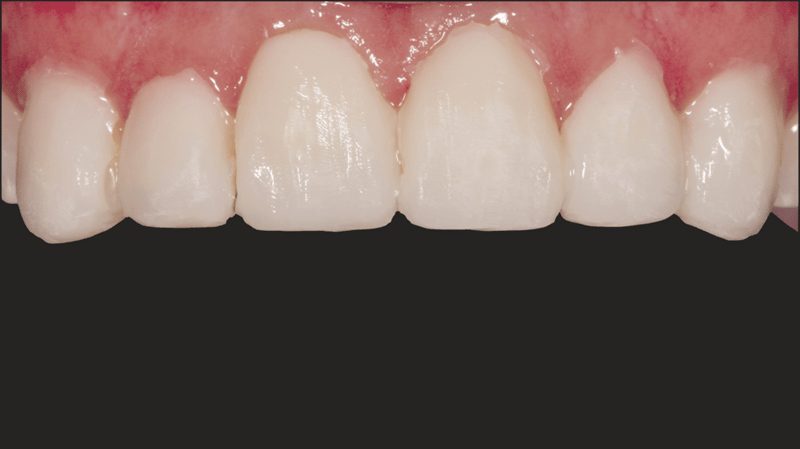

- Resultaat van het cementeren: De definitieve cementatie resulteerde in functionele, mooi aangebrachte veneers.

- Faciale anatomie: Voor het creëren van de faciale anatomie werd gebruikgemaakt van bolvormige en lange, dunne diamantboren. Met een gelobde diamantboor werden de lijnen van Retzius aangebracht. De eerste polijstbewerking werd gedaan met Jiffy™ Natural-polijstinstrumenten. De definitieve glans werd bereikt met Ultradent™ Diamond Polish Mint en de Jiffy™ Goat Hair Brush (niet beschikbaar in Europa), om de tertiaire anatomie niet te verwijderen.

Met de ingreep konden de esthetische problemen van de patiënte met succes worden aangepakt; de verkleuring van de frontelementen in de bovenkaak is gemaskeerd en er is nu sprake van een natuurlijk, evenwichtig beeld ten opzichte van de frontelementen in de onderkaak. Het gebruik van directe adhesieve composietveneers zonder preparatie bleek een conserverende, zeer effectieve oplossing te zijn die zowel tegemoetkwam aan de lastige financiële situatie van de patiënte als aan de behoefte aan een minimaal invasieve behandeling.